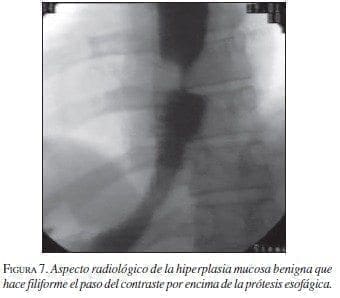

Diferentes estudios del comportamiento de las EMA en la vía biliar (Maccioni, 1992 y Veis, 1994) demuestran una evolución diferente para las estenosis malignas con respecto a las benignas; en las últimas más frecuentemente hay obstrucción producida por hiperplasia benigna mucosa demostrada en estudios que confirman histológicamente la misma. Una explicación a esta diferencia es dada por el mayor tiempo de interacción de las prótesis con los tejidos vecinos en los casos de obstrucciones benignas, lo que no sucede en las malignas. (Cwikiel, 1993; Chen, 2000; Mayoral, 2000) (figuras 6 y 7).

![]() |